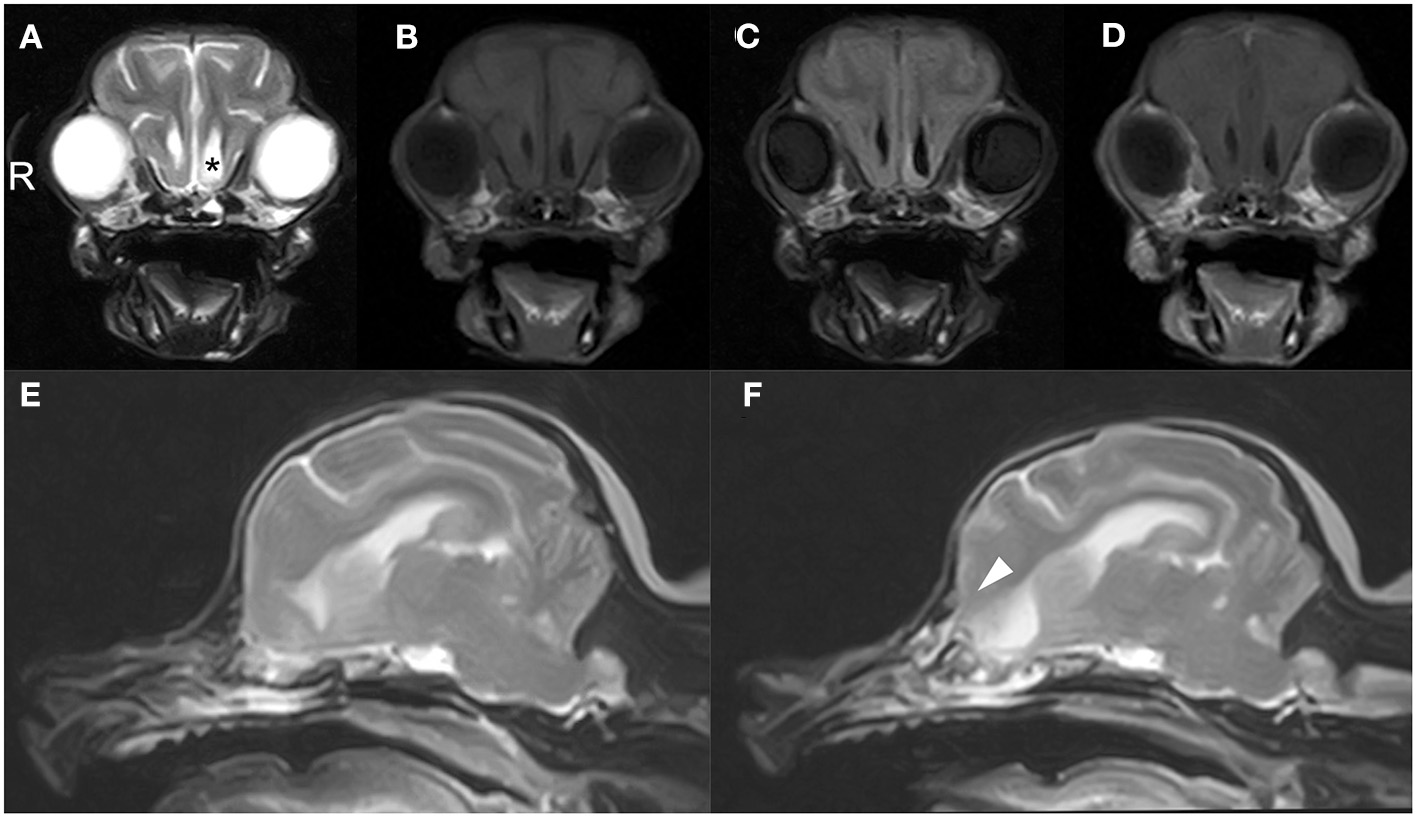

CT and MRI were undertaken to examine the cerebrum and diencephalon. Anesthesia was induced by propofol (MSD Animal Health, Tokyo, Japan) at a dose of 5.0 mg/kg and was maintained by isoflurane (MSD Animal Health). MRI was performed using a 0.4 T unit (APERTO Inspire version V5.0M; Hitachi Healthcare Systems, Osaka, Japan). The sequences included T2-weighted images (T2WI; TR, 2,800 ms; TE, 120 ms) of transverse and sagittal views, fluid-attenuated inversion recovery (FLAIR; TR, 6,900 ms; TE, 120 ms) of transverse view, T1-weighted images (T1WI; TR, 300 ms; TE, 14.3 ms) of transverse view, and postcontrast T1WI (gadoteridol, 0.2 mL/kg intravenous administration) of transverse view. Brain MRI revealed irregularities in the left cribriform plate compared to the right cribriform plate (Figures 1E,F). Also observed were the olfactory recess of the left lateral ventricular enlargement and irregular hyperintensity around the olfactory recess of the left lateral ventricle (Figures 1A–C). No signs of contrast enhancement were observed on postcontrast T1WI (Figure 1D). No other cerebral parenchymal lesion was observed. The CT scan (Activion16, Toshiba Medical Systems, Tochigi, Japan) was performed with a pitch of 0.9 mm, scan thickness of 0.5–2.00 mm, 100 mA, and 120 V. For contrast-enhanced imaging, the dog was administered with 2 mL/kg of non-ionic contrast medium (Ominipaque, GE Healthcare, Chicago, IL). Cranial CT revealed a defect of the left cribriform plate was observed (Figure 2A). No contrast enhancement was noticed. An irregular lesion in the left nasal cavity around the left cribriform plate was also observed (Figure 2B), for which the differential diagnosis was neoplasia, inflammation, or meningoencephalocele. No CSF tap was performed, because of malformation of the occipital bone. After CT and MRI examination, a sample of persistent nasal discharge was collected for cytological examination and for bacterial culturing. The bacterial culture results were negative, and cytologic evaluation showed non-infectious inflammation. Treatment was started with phenobarbital (4 mg/kg, BID).

Figure 2. Cranial CT images of a 12-year-old Yorkshire terrier with epileptic seizures and nasal discharge (A,B). On the coronal and sagittal bone condition images at the cribriform plate level (A,B, respectively), a defect of the left cribriform plate is noticeable (white arrowheads). On the coronal soft tissue images at the level of the optic nerve (A), an irregular lesion in the left nasal cavity around the left cribriform plate is observed (black asterisk).